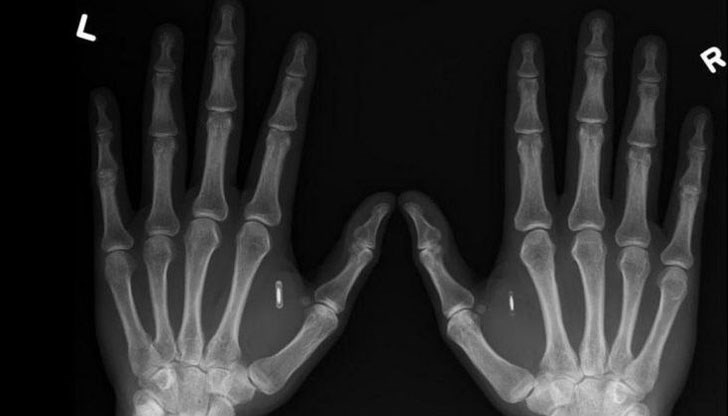

Спринцовката се плъзга между палеца и показалеца. След това, само с едно кликване микрочип се инжектира под кожата на човек. И ето - още един киборг е готов.

Това не е сцена от поредния научно-фантастичен филм, а ежедневие в шведския стартъп хъб Epicenter. Компанията имплантира на своите служители микро чипове с размера на оризово зрънце.

Подкожните импланти се ползват вместо познатите ни чип карти - с тях се отварят врати; ползва се техника - принтери, скенери; пазарува се от кафенето в офиса; извършват се различни други операции.

Малкият имплант стои между палеца и показалеца и не представлява опасност за здравето на служителите. той не е и проследяващо устройство, а само регистрира извършваните операции в офиса.

Чиповете ползват технологията Near Field Communication (NFC), същата като при безконтактните кредитни карти или мобилните разплащания. Когато се активира от четец на няколко сантиметра, малко количество информация може да се предава между двете устройства чрез електромагнитни вълни. Имплантите са "пасивни", т.е. те съдържат информация, която други устройства могат да разчетат, но самите те не могат.